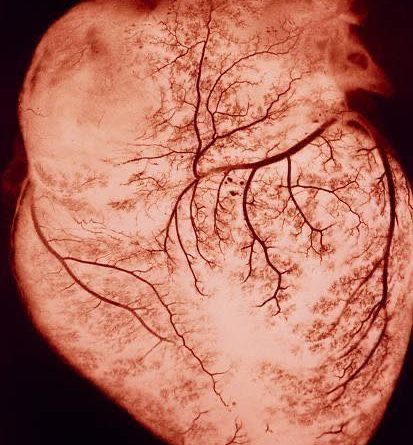

ออกกำลังกาย เร่งให้เลือดไหลเข้าระบบหลอดเลือดหัวใจแรงขึ้น ซ้อมให้ผนังหลอดเลือดรับรู้ถึงแรงของเลือด มันจึงวางแผนสร้าง ‘โรงงานสร้างก๊าซ nitric oxide’ (eNOS) เอาไว้เยอะๆ ทำให้หลอดเลือดหัวใจมีก๊าซนี้ คอยขยายหลอดเลือด คอยยับยั้งการเกิดลิ่มเลือดตอนช่วงวิกฤติไม่ให้ใหญ่มาก

แถมการไหลของเลือดที่มามากขึ้นนี้ ยังช่วยให้เกิดการแผ่ขยายเครือหลอดเลือดฝอยมากขึ้น เวลาอยู่ในช่วงวิกฤติ มีโอกาสสูงที่ตำแหน่งพื้นที่หลอดเลือดข้างเคียง ดันเลือดมาช่วยเลี้ยงได้ (Collateral circulation)